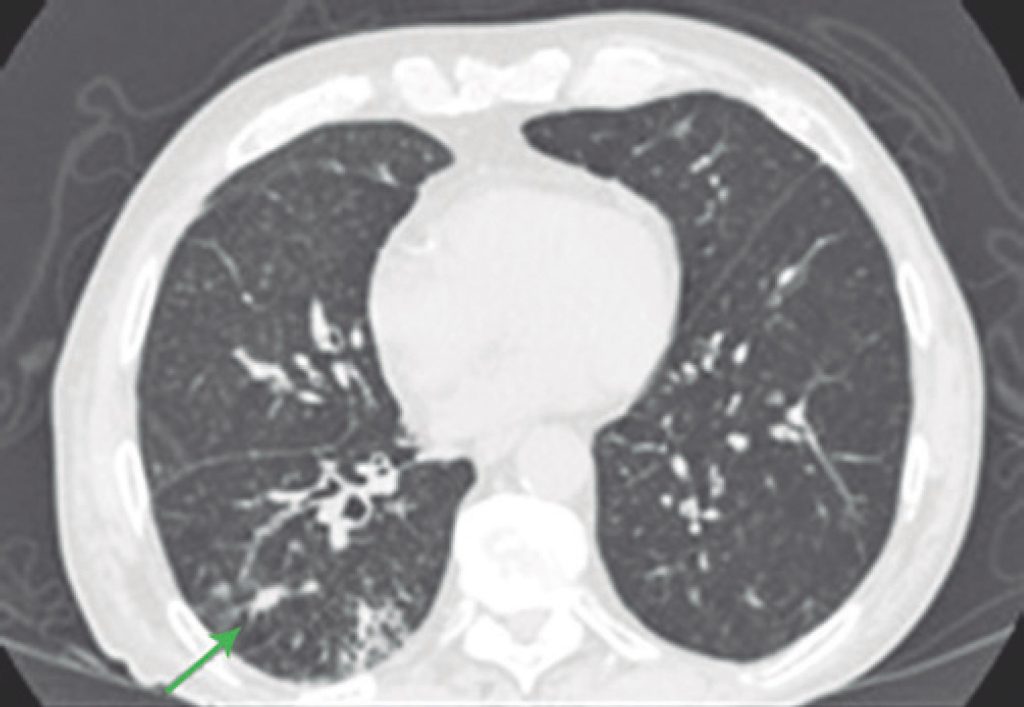

A pneumonite secundária à imunoterapia é uma complicação rara, com incidência estimada em cerca de 3%. No entanto, trata-se de uma intercorrência de difícil diagnóstico e com grande morbidade, que tem se tornado um desafio para oncologistas e emergencistas. Foram revisados os casos de cinco pacientes que fizeram uso de anti-PD1 (program cell death receptor antagonist 1) para tratamento antineoplásico e que evoluíram com quadro de pneumonite induzida pelo tratamento. Todos os pacientes apresentaram sintomas respiratórios em vigência de tratamento, com imunoterapia e presença de alteração radiológica em vidro fosco. Dentre estes pacientes, apenas um apresentou pneumonite grau 5, com atraso na introdução de corticoidoterapia, indo a óbito em decorrência do quadro. Os outros quatro pacientes apresentaram pneumonite grau 2, sintomática, sendo tratados com corticoidoterapia e evoluindo com melhora clínica e radiológica. Dois pacientes mantiveram o tratamento após o episódio de pneumonite, sem novas complicações pulmonares posteriores, até o momento. A pneumonite induzida por imunoterapia, apesar de ser um evento pouco frequente, pode acarretar grande morbidade, além de ser potencialmente fatal, cabendo à equipe médica ter atenção aos sintomas mais comuns, como tosse e dispneia, para diagnóstico precoce e tratamento efetivo, com uso precoce de corticoide.